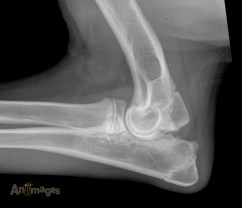

Pour vous préparer à ce cours spécialisé, on vous suggère fortement de revoir les notes de cours et Powerpoint fournies pour le cours DMV3236 de cet automne. Les notions qui ont été abordées seront revues, mais l’emphase cette fois sera mise sur les pathologies du système locomoteur du chien et du chat (dysplasie des hanches et du coude, etc.). Pour un aperçu de la matière livrée en classe (Powerpoint de 2015 sous format PDF), cliquez ICI. Vous recevrez le lien après le cours de lundi pour télécharger la présentation mise-à-jour pour aider avec le petit quiz qui suivra ce cours, de même que les instruction et liens pour le quiz qui suivra.